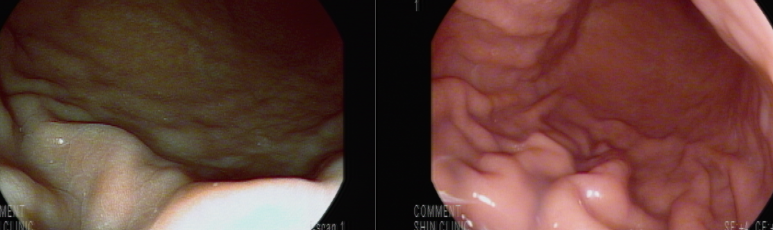

체부 중앙 후벽으로 점막이 딸려올라가고 동반된 창백한 점막 소견으로 넓은 얕은 궤양상 병변이 있었을 것으로 의심됨

일부 발적도 동반하고 있어 MALToma 배제가 필요